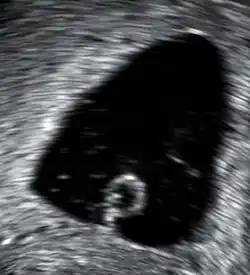

In the case of blood loss, pain, or both, transvaginal ultrasound is performed. If a viable intrauterine pregnancy is not found with ultrasound, blood tests (serial βHCG tests) can be performed to rule out ectopic pregnancy, which is a life-threatening situation.[107][108]

A miscarriage may be confirmed by an obstetric ultrasound and by the examination of the passed tissue. When looking for microscopic pathologic symptoms, one looks for the products of conception. Microscopically, these include villi, trophoblast, fetal parts, and background gestational changes in the endometrium. When chromosomal abnormalities are found in more than one miscarriage, genetic testing of both parents may be done.[109]

Ultrasound criteria

A review article in The New England Journal of Medicine based on a consensus meeting of the Society of Radiologists in Ultrasound in America (SRU) has suggested that miscarriage should be diagnosed only if any of the following criteria are met upon ultrasonography visualisation:[110]